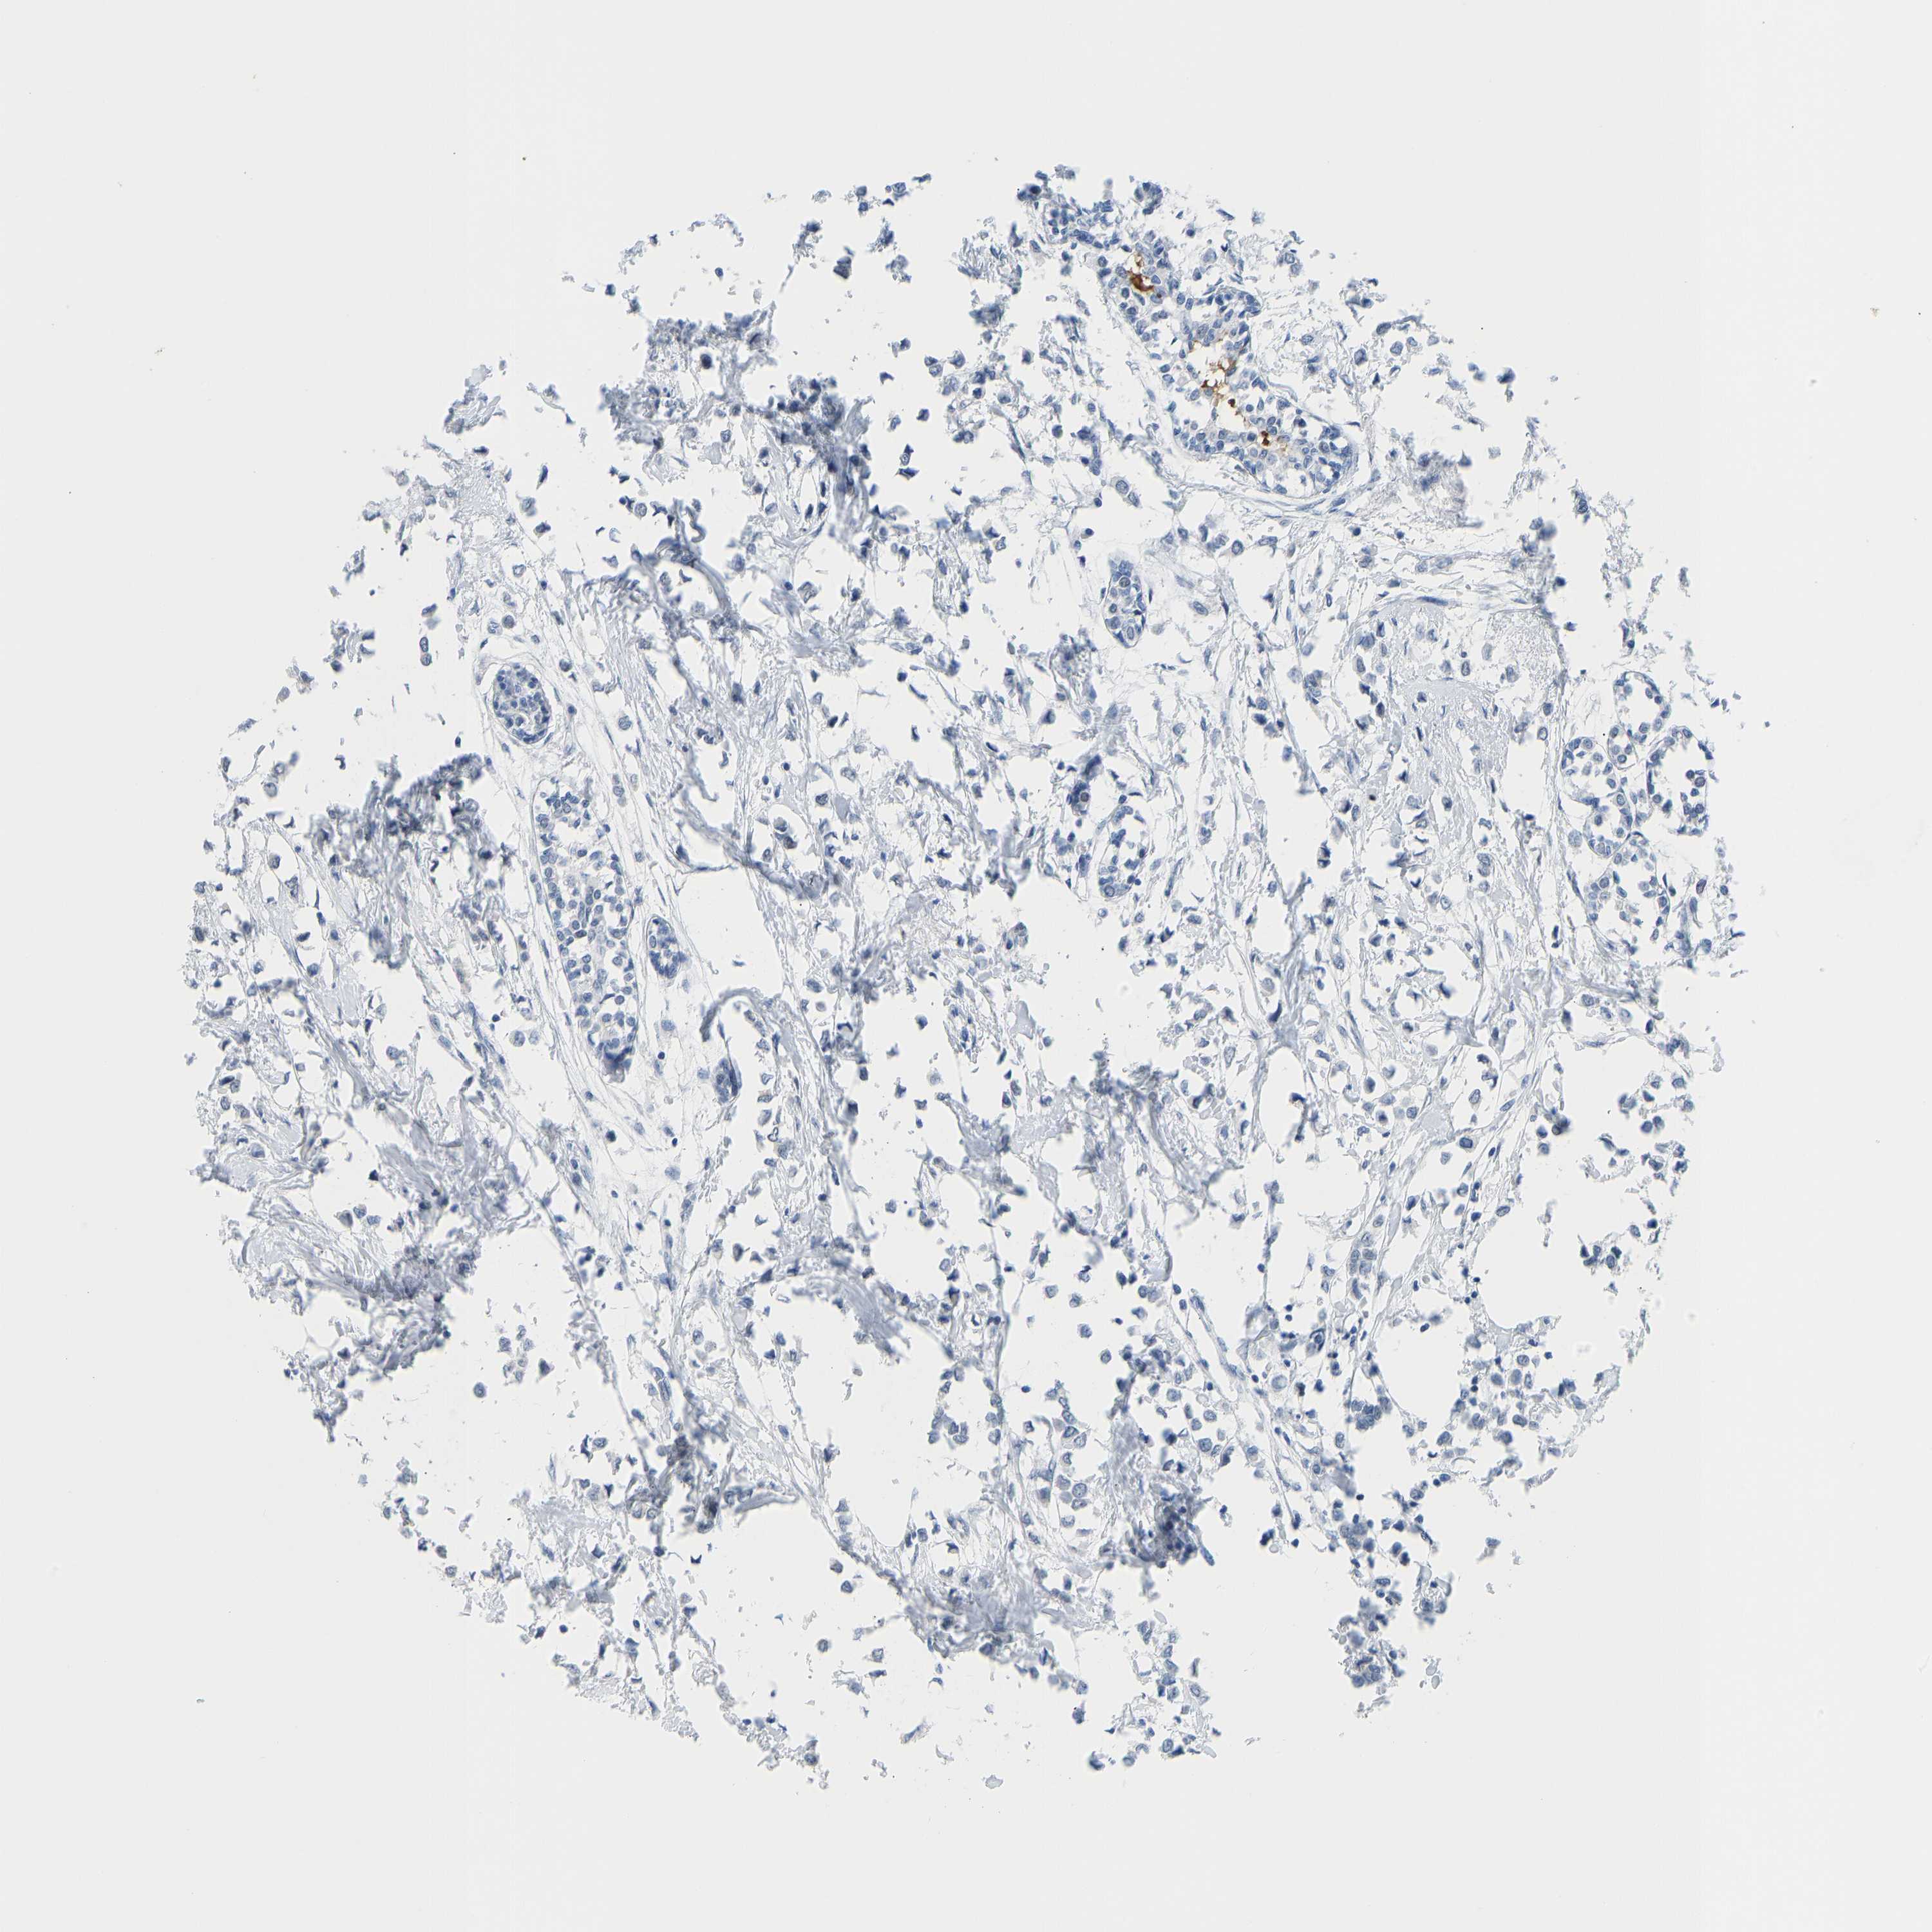

BRCA TCGA BRCA VALIDATION PROTEIN EXPRESSION

ANTIBODIES

AND

VALIDATION